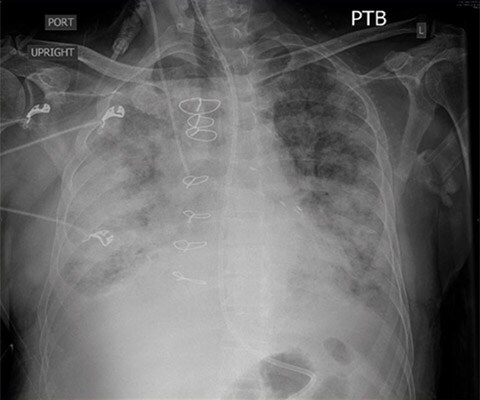

Given his renal failure and anticipated limitations to aggressive diuresis with medical therapy, arrangements were made to emergently intubate the patient, augment ionotropic support, escalate diuresis attempts with diuretics while calling the family to discuss care options including likely need for dialysis. As the patient was being prepped for intubation, X-ray imaging was obtained confirming the diagnosis of pulmonary edema.

POCUS with a small, extremely portable device had allowed for convenient and rapid evaluation, diagnosis, and intervention in a complex patient. A repeat chest X-ray just one hour after intubation showed marked improvement in the patient’s pulmonary edema.